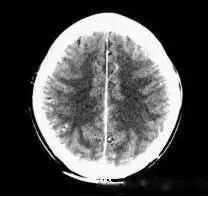

(機器故障偽影:常為環(huán)形或同心圓狀高密度偽影)

2、機器故障偽影的形狀機器故障所至偽影的形狀各種各樣,有非同心圓形和同心圓形(單同心圓和多同心圓、直線形、柵格形條紋狀)、星狀,還有不規(guī)則形,一般來說.根據(jù)偽影形狀可大致區(qū)分為機器哪一個系統(tǒng)故障所致。

如:單同心圓可能為通道板故障、連續(xù)屏蔽多個通道,多同心圓可能為環(huán)境溫濕度變化較大,AD控制板故障、線性電源問題、高壓線性電源問,滿屏斜條或直線可能為高壓系統(tǒng)故障·不規(guī)則形則可能為球管老化所致。